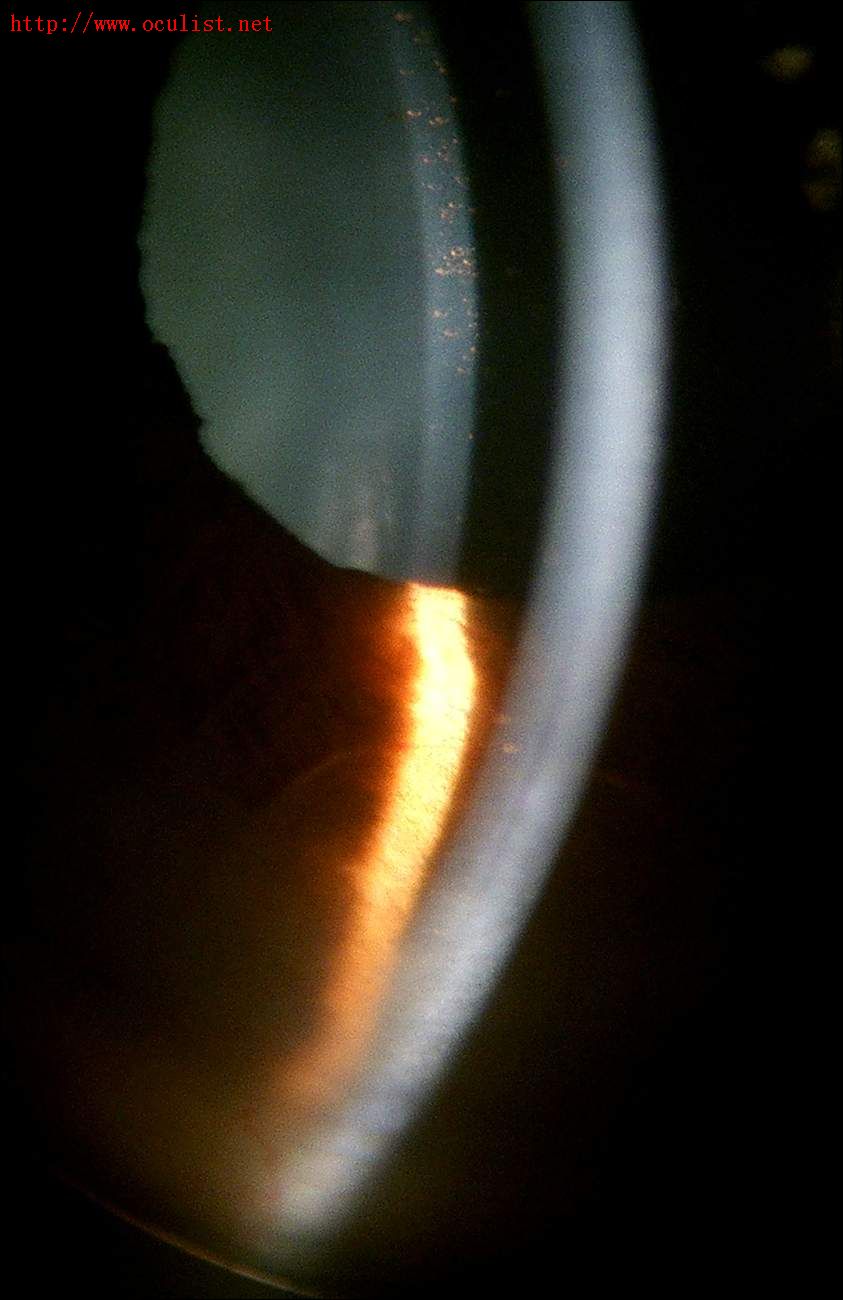

只是使用普通的数码相机就可以拍到裂隙灯下的漂亮照片!

数码相机拍摄的裂隙灯照片